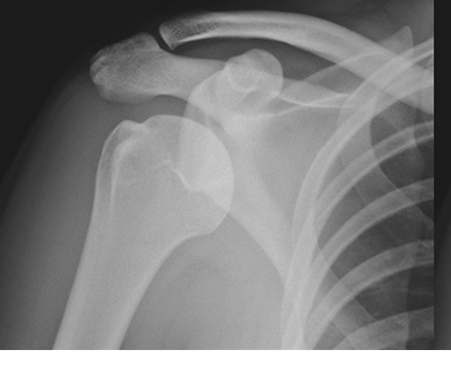

Achieve Your Comeback: Orthopedic Rehab to Get Back to Your Best

Looking for accurate information on Achieve Your Comeback: Orthopedic Rehab to Get Back to Your Best? Orthopedic rehabilitation is a specialized therapy aiding recovery from musculoskeletal injuries or surgeries affecting bones, muscles, tendons, and ligaments. It uses exercise, manual therapy, and modalities to improve range of motion, strength, and flexibility. This therapy is crucial for reducing pain, restoring functional ability, and getting you back to your best, enhancing overall quality of life.